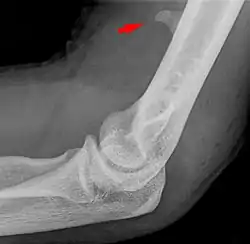

![]() Larger supracondylar process seen on a lateral radiograph of the elbow | |

The supracondylar process of the humerus (also known as an avian spur) is a variant bony projection on the anteromedial aspect of the upper arm bone (humerus), about 5–6 cm above the medial epicondyle.[1] It is directed downward, forward and medially pointing to the medial epicondyle. A fibrous band, Struthers ligament, may connect this process to the medial epicondyle.[2] This variation has a prevalence of 0.68% and is significantly more common in women than in men.[3]